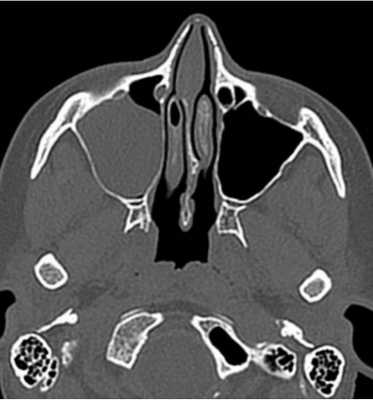

Магнитная томография околоносовых пазух: левосторонний сфеноидит